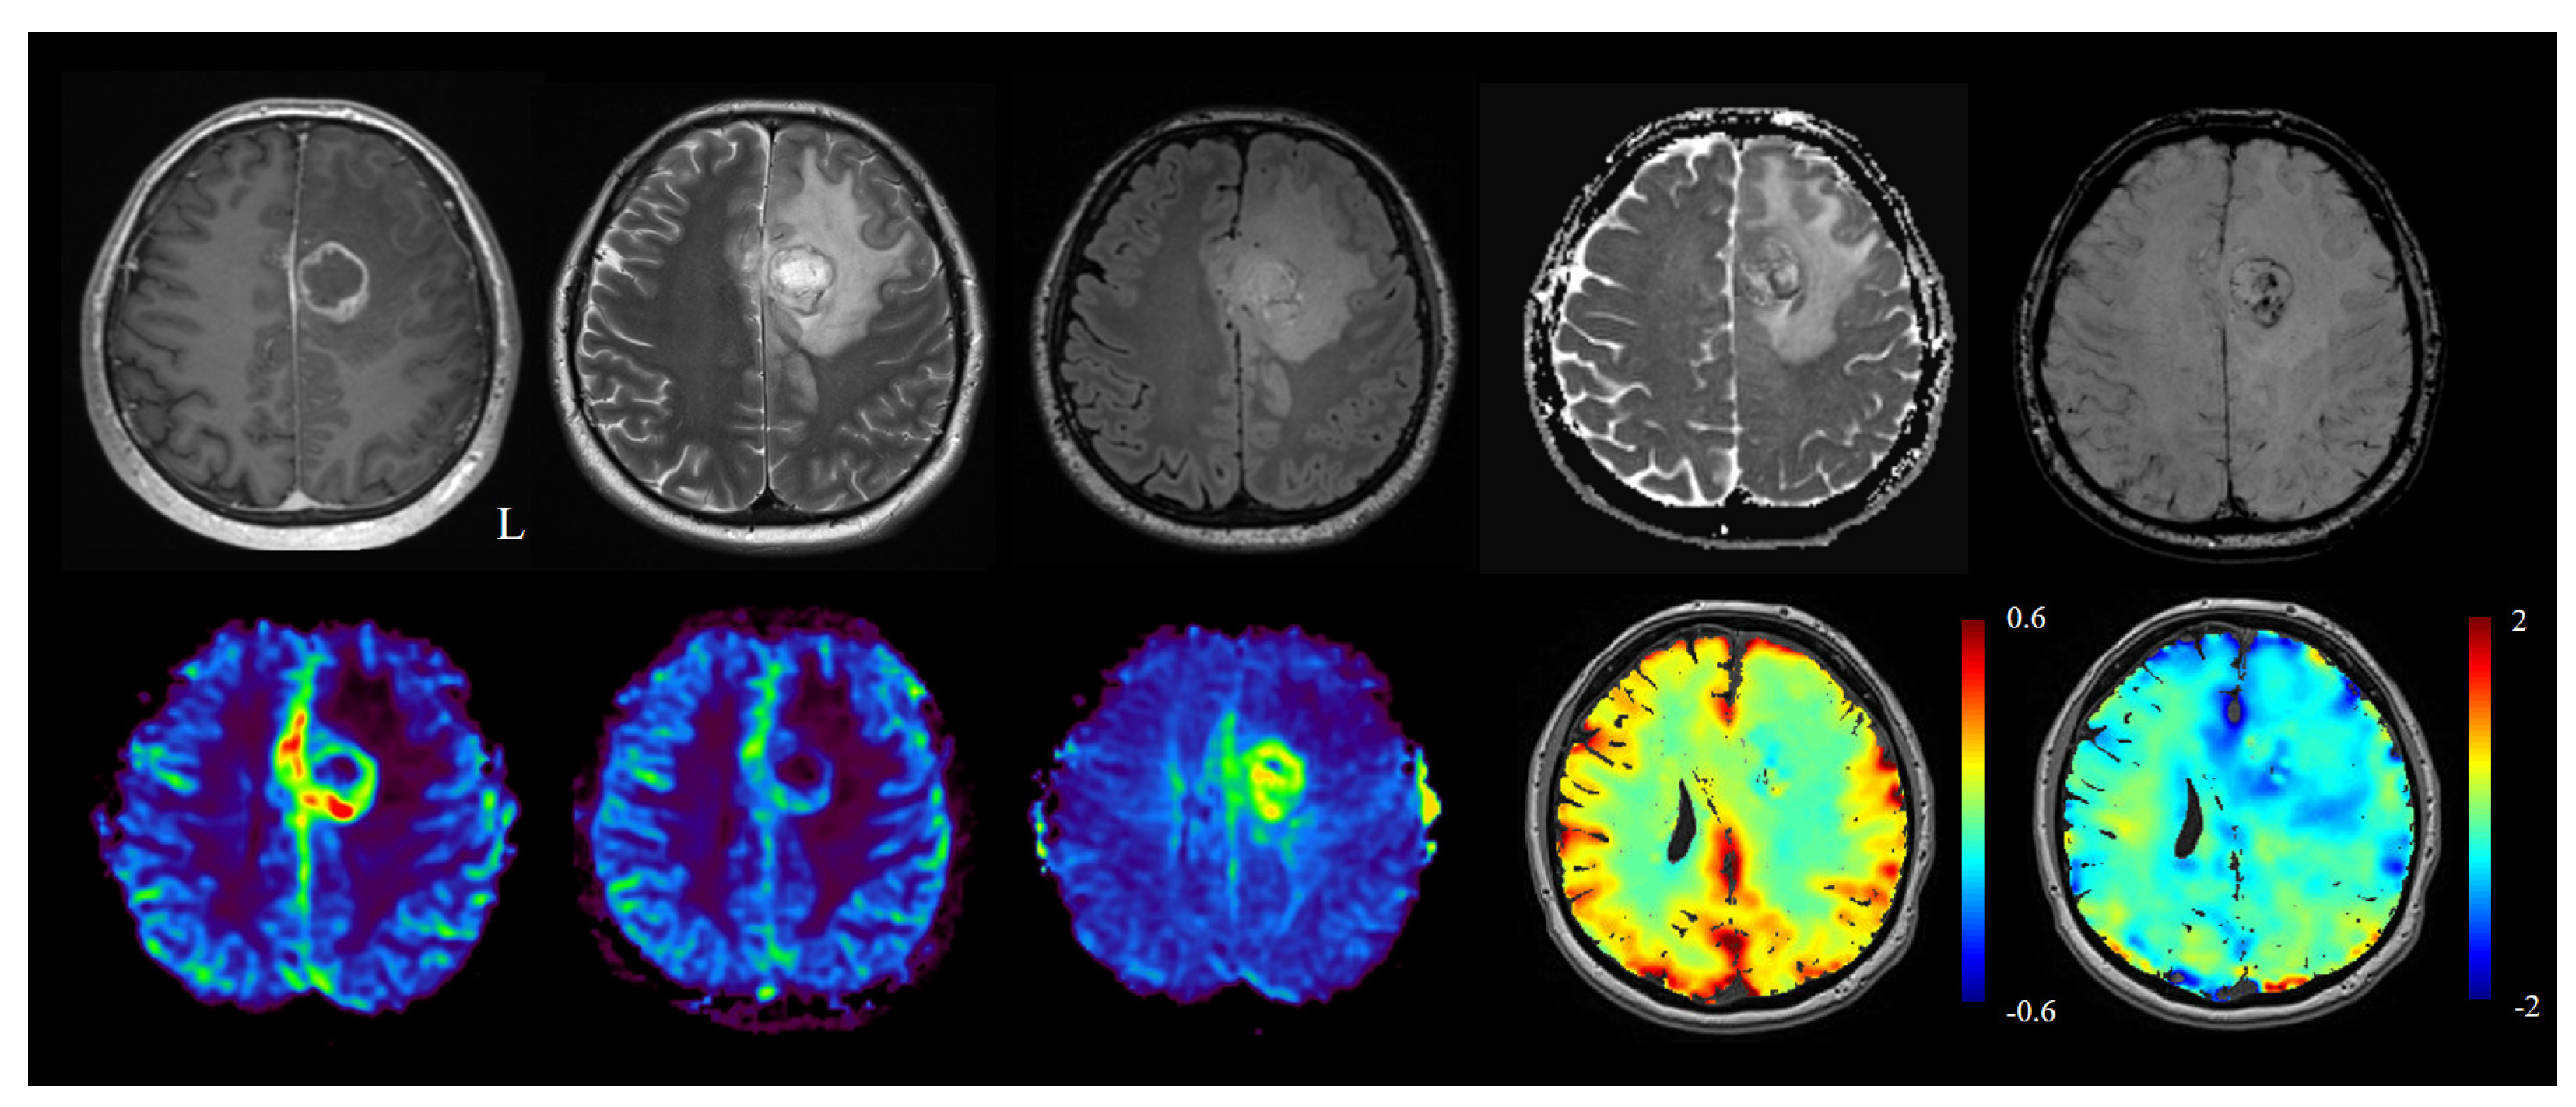

- Stumpo, V.; Sebök, M.; van Niftrik, C.H.B.; Seystahl, K.; Hainc, N.; Kulcsar, Z.; Weller, M.; Regli, L.; Fierstra, J. Feasibility of glioblastoma tissue response mapping with physiologic BOLD imaging using precise oxygen and carbon dioxide challenge. Magn. Reson. Mater. Phy. 2021. online ahead of print. [Google Scholar] [CrossRef] [PubMed]